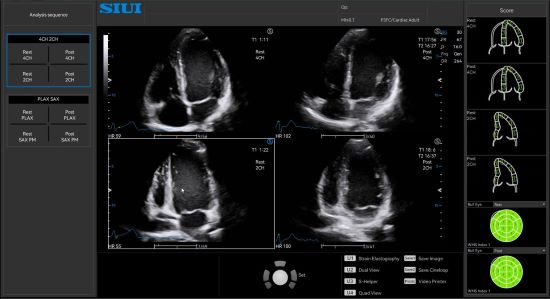

Stress Echo analyzes myocardial motion at rest and under stress to help evaluate how coronary arteries respond to the stress.